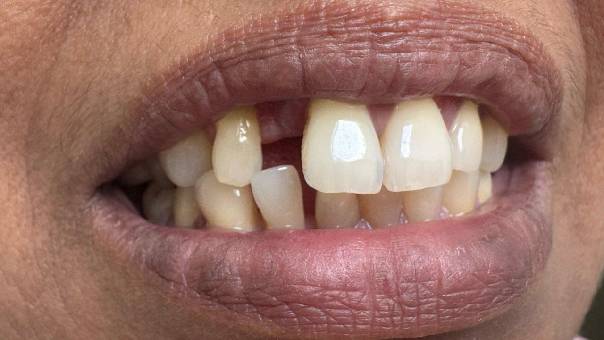

Patient Concern: The patient presented with composite fillings on his upper anterior teeth (from right canine to left canine). However, the results from previous dental work left much to be desired. There was a clear shade mismatch between the fillings and the natural teeth, which made the restorations very noticeable when he smiled or spoke.

More significantly, the patient had a reverse curve in the upper anterior region—a condition where the natural curvature of the smile arch is inverted. This disrupted the overall smile aesthetics.

Treatment Plan:

Root Canal Treatment for all upper anterior teeth (from right canine to left canine) to manage any underlying pathology and provide a stable foundation for prosthetic work

Placement of Zirconia joined crowns across the anterior segment to restore form, function, and aesthetics

Smile designing using crowns to correct the reverse curve and improve facial harmony